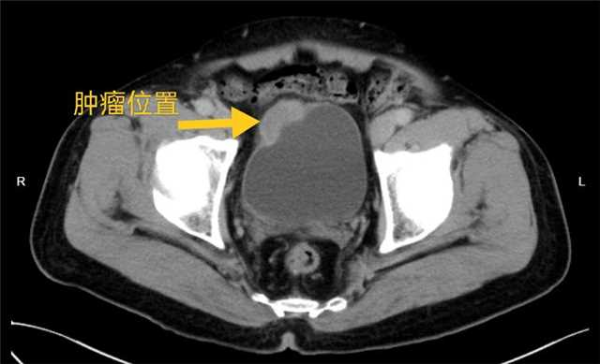

右肾肿瘤位置,大小约58mm×59mm×53m

刘久敏主任会诊后指出,患者完善膀胱肿物病理活检证实为浸润性尿路上皮癌,结合患者盆腔增强CT检查,肿瘤较大,侵犯膀胱壁,须根治性膀胱切除才能治愈病情,避免肿瘤扩散与转移。刘久敏主任与县人民医院泌尿外科医护团队为郭大叔制定治疗方案:尽早行微创腹腔镜下根治性膀胱切除术+双侧输尿管腹壁造口术。